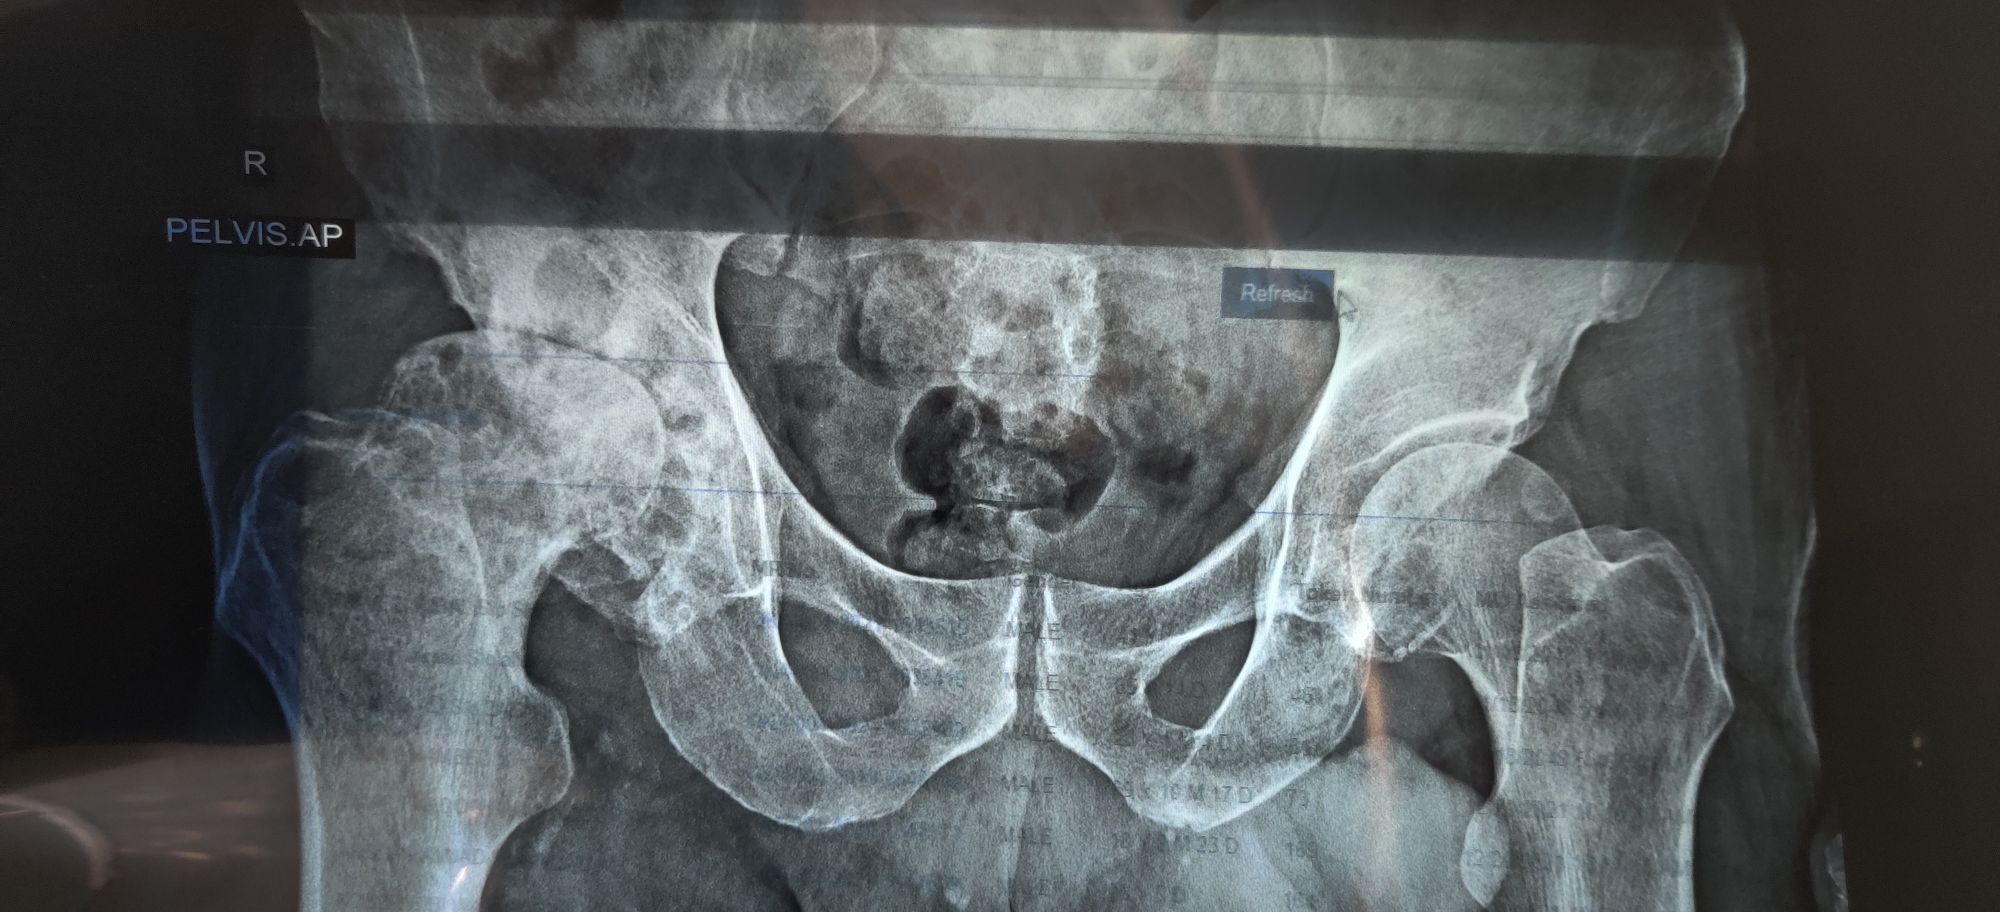

R neck of femur fx

Ortho

Femur

Fractured